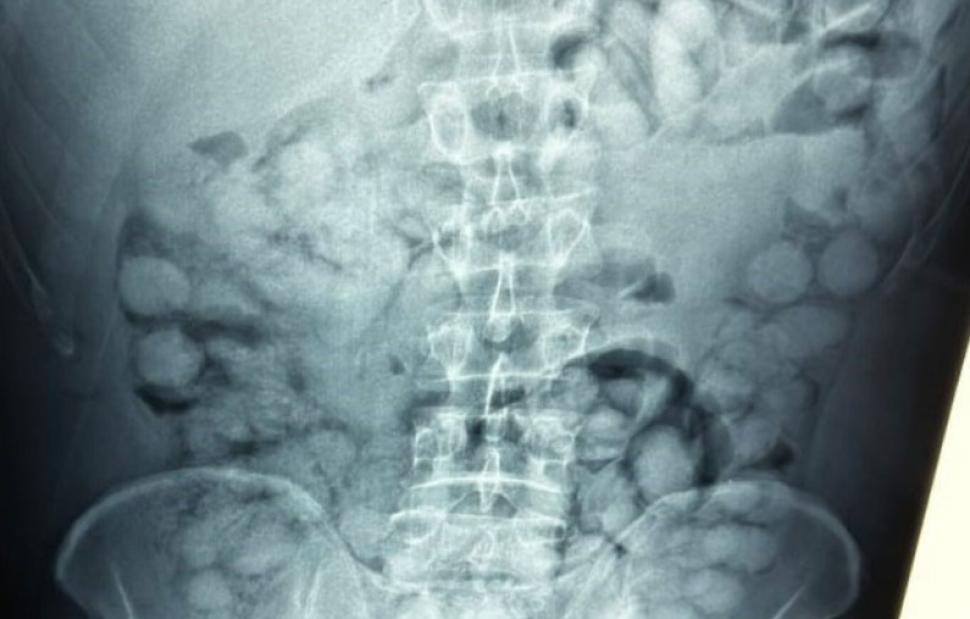

Ένας άνδρας, από τη Βραζιλία, συνελήφθη το πρωί στο αεροδρόμιο «Ελευθέριος Βενιζέλος», κατηγορούμενος ότι είχε καταπιεί σημαντική ποσότητα κοκαΐνης.

Σύμφωνα με την Αστυνομία, ο άνδρας έφτασε στην Αθήνα, μέσω Παρισιού και στον έλεγχο που διενεργήθηκε, διαπιστώθηκε ότι είχε καταπιεί περίπου 100 συσκευασίες κοκαΐνης.